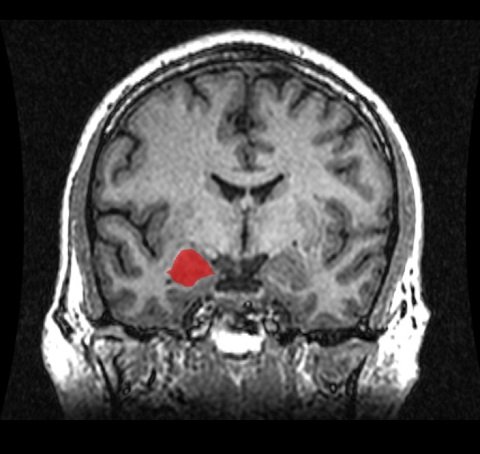

これまでの研究でも扁桃体と海馬がうつや不安障害に関係があると考えられてきたが、具体的にどのように影響を及ぼしているのかはわからなかった。しかし今回の研究で、うつや不安を感じている時には扁桃体と海馬がベータ波で“同期”していることがわかったのである。

右の扁桃体 画像は「Wikipedia」より今回の発見は精神医療の治療法の開発に有効に活用できるものであるとソハール博士は主張している。例えば扁桃体と海馬の活動を制御したり、結びつきを弱めたりすることができればうつや不安を緩和することができるようになるかもしれない。